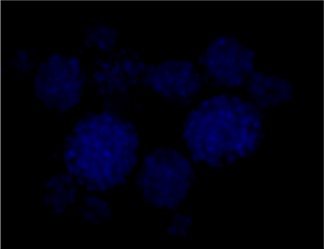

Immunofluorescence staining of Src and Phospho-Src

P-SRC Tyr416

DAPI